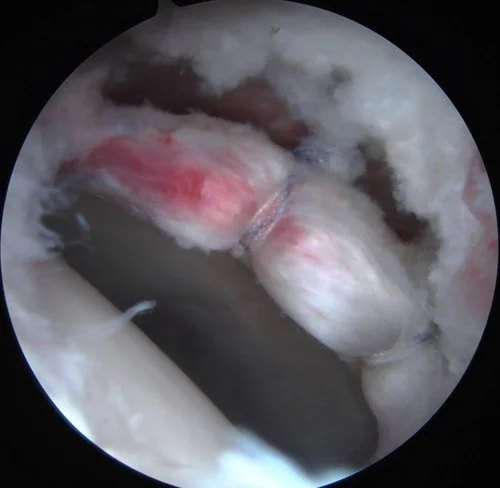

During hip arthroscopy, your surgeon inserts a small camera, called an arthroscope, into your hip joint. The camera displays pictures on a video monitor, and your surgeon uses these images to guide miniature surgical instruments.